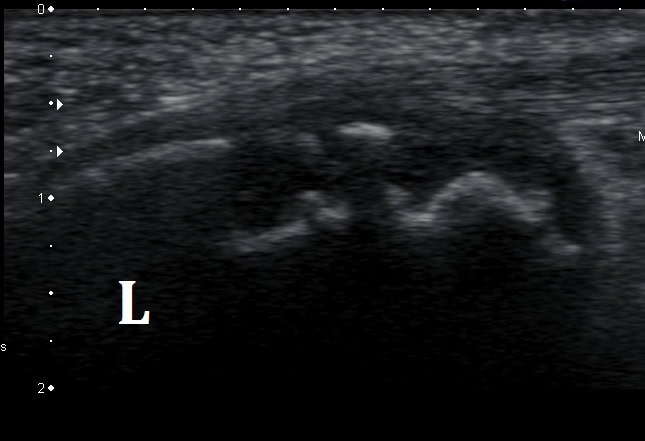

Ultrasound Imaging is also beneficial when diagnosing Severs disease. Ultrasound images of the apophysis are usually fragmented with increased vascularisation.

(Fragmentation of the calcaneal apophysis as seen on ultrasound)